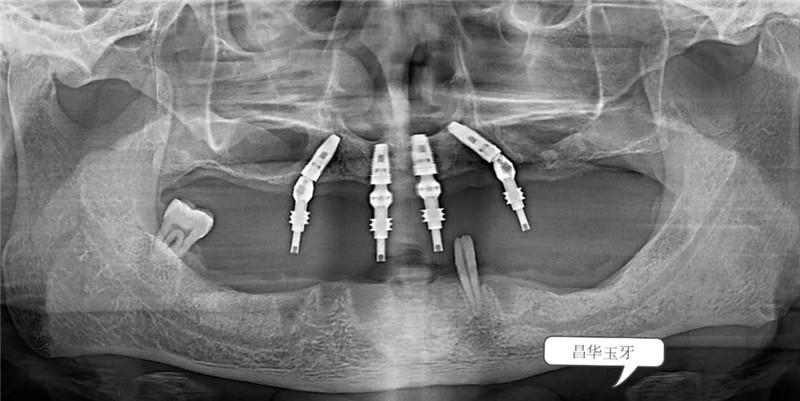

根據(jù)患者的口內(nèi)情況,結(jié)合X光片,為患者設(shè)計(jì)全口牙種植All-on-4。并在一系列的術(shù)前準(zhǔn)備之后,我院特邀——省口腔家白彭主任為患者植入4顆植體,手術(shù)微創(chuàng)、全程無痛,并在12月20日傍晚,白主任為患者裝上上半口固定牙冠,患者很滿意。